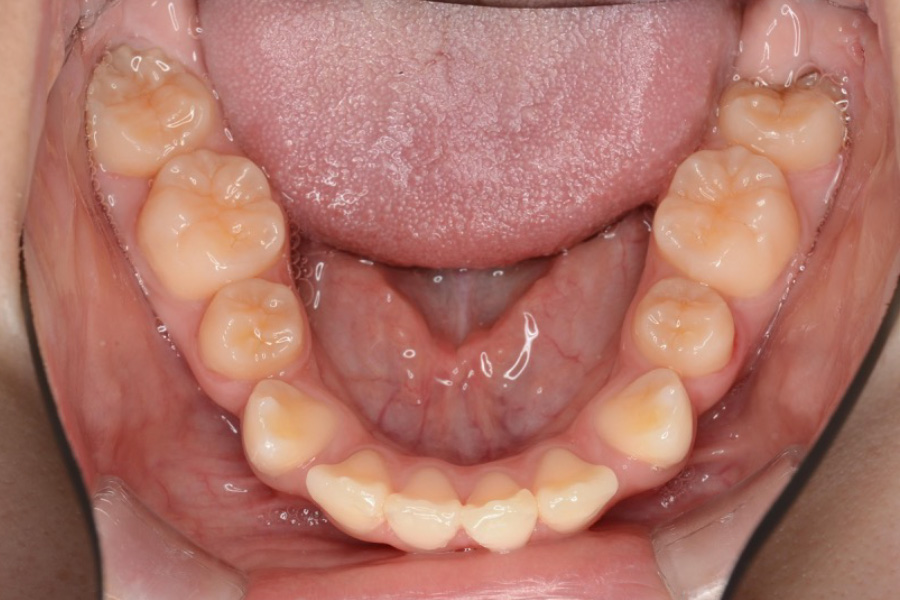

治療前

主訴 歯のスペースを閉じたい

治療内容 インビザライン矯正

非抜歯